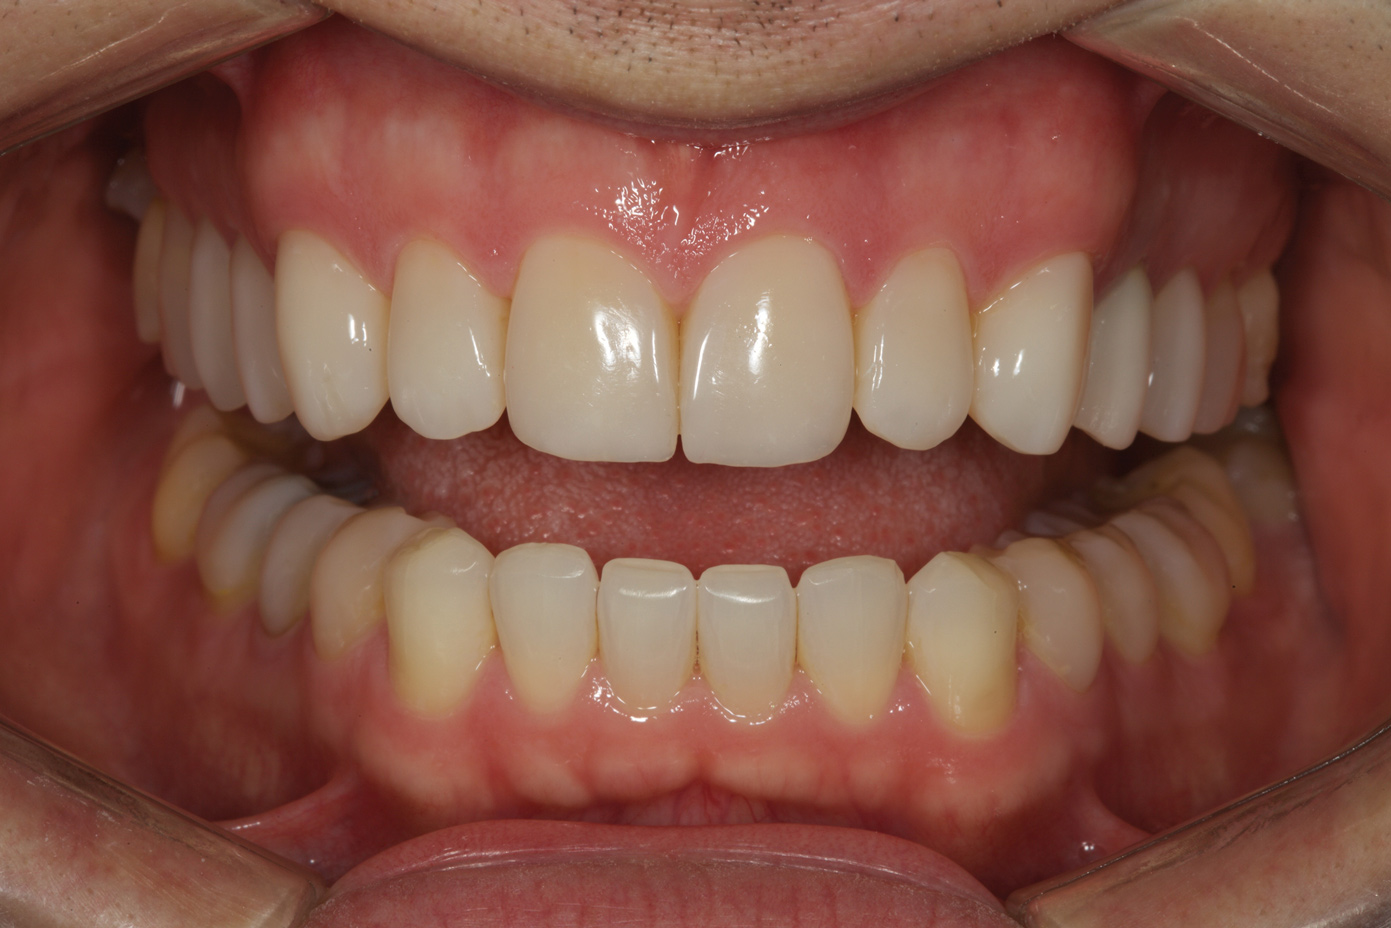

Fig 11. Postoperative retracted view.

Figure 11

Following caries treatment and tooth preparation (Figure 6), teeth Nos. 4 through 13 were restored with direct composite veneers in stages (Figure 7 through Figure 9). Using a hybrid composite for the lingual shelf and dentin layer provides wear resistance and strength for the restoration.14,15 (The lowest wear rates for restorations and the opposing dentition occur with metal alloys, machined ceramics, and microfilled hybrid resin composites. Any adjusted and unpolished porcelain surface would elicit the most wear on the opposing teeth.11)After the composite veneers were finalized, a monolithic lithium disilicate crown was placed on tooth No. 12 during a subsequent appointment, and occlusal equilibration was carried out. Final photographs were taken a couple of weeks later (Figure 10 through Figure 14).

The use of transitional bonding techniques can allow complex cases to be treated in a cost-effective and timely manner. Furthermore, occlusal and esthetic designs can be evaluated while the maximum amount of tooth structure is conserved.